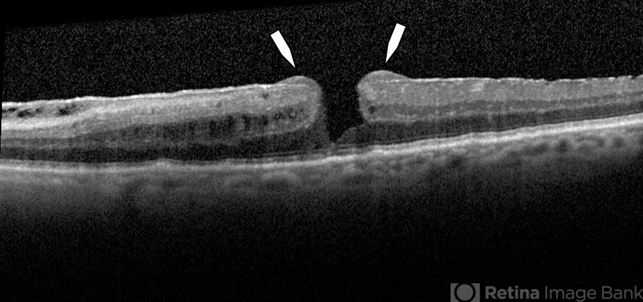

- lamellar macular hole

Optical coherence tomography system

Heidelberg Spectralis - Description

- Spectral domain OCT of lamellar macular hole with lamellar hole-associated epiretinal proliferation (LHEP) indicated by white arrows.